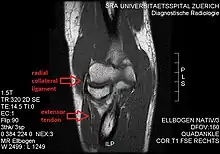

MRI of the elbow (T1 weighted) showing an unimpaired radial collateral ligament and extensor tendon.